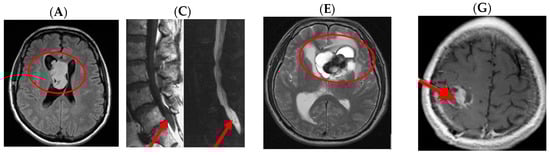

- Radiopedia; Jones, J.; Gaillard, F.; et al. Glioblastoma. Available online: https://radiopaedia.org/articles/glioblastoma (accessed on 27 March 2017).

- Radiopaedia. Spine Ependymomas. Available online: https://radiopaedia.org/articles/spinal-ependymoma (accessed on 27 March 2017).

- Radiopaedia. Ependymoma. Available online: https://radiopaedia.org/cases/ependymoma-lateral-ventricle (accessed on 27 March 2017).

- CERN Foundation. Adult Ependymoma Images. Available online: http://www.cern-foundation.org/education/diagnosis/adult-ependymoma-images (accessed on 27 March 2017).